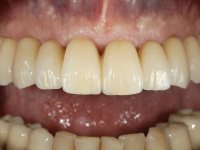

O paciente apresentou-se na consulta com intenção de fazer uma reabilitação estética e funcional completa.

Paciente do sexo masculino, com 64 anos de idade e não fumador. Apresentava uma prótese combinada superior composta por uma ponte metalo-cerâmica fixa de 6 elementos (1.3,1.2,1.1,2.1,2.2, e 2.3) e uma prótese esquelética superior também com 6 elementos. No maxilar inferior apresentava duas pontes metalo-cerâmicas, uma de 3 elementos no 4º quadrante e outra de 2 elementos no 3º quadrante. A adaptação das pontes estava comprometida e esteticamente não satisfaziam o paciente. A higiene oral não era satisfatória.

Foi proposto ao paciente fazer uma reabilitação total superior sobre implantes com colocação de uma prótese provisória aparafusada em carga imediata. Após osteointegração seria colocada uma prótese fixa metalo-cerâmica, se possível, com fixação aparafusada. No maxilar inferior foi proposta a colocação de 3 implantes no 4º quadrante para suportar uma ponte metalo-cerâmica de 3 elementos.

Realizada uma TAC, foi planificada a colocação de 6 implantes no maxilar superior. Foi decidida a colocação de dois implantes na zona dos incisivos centrais, dois implantes na zona dos caninos e dois na zona dos segundos pré-molares. A ausência de estrutura óssea na zona distal do primeiro quadrante implicava a realização de uma regeneração óssea no seio maxilar direito. A cirurgia foi realizada e após a colocação dos implantes foi feita a impressão para confeção de uma prótese provisória metalo-acrílica aparafusada para colocação em carga imediata no dia seguinte. O implante colocado na zona do seio maxilar direito não foi colocado em carga. Passados 6 meses foi realizada a impressão aos 6 implantes com técnica de moldeira aberta e foram confecionados os modelos de trabalho. Numa consulta seguinte foram montados os modelos de trabalho em articulador semi-ajustável utilizando o arco facial e a relação inter-maxilar obtida com a prótese provisória. Foi feita uma muralha de silicone sobre a ponte provisória com o objetivo de orientar o trabalho laboratorial. Realizada a infra estrutura metálica aparafusada esta foi provada em boca e finalmente após colocação de cerâmica o trabalho foi colocado definitivamente. Como passaram vários meses após a realização da primeira TAC foi feita uma segunda para planificar a colocação de implantes no 4º quadrante. Colocaram-se 3 implantes na mesma sessão em que foi feita a extração dos pilares da ponte. Estes implantes foram posteriormente reabilitados com uma ponte metalo-cerâmica aparafusada de três elementos.